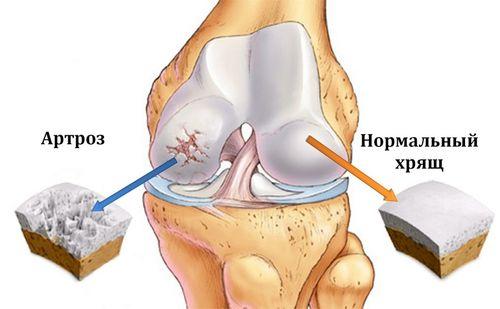

- артроз характеризуется деформацией и разрастанием краев костей, уменьшением хрящевой прослойки;

Артроз — это распространенная суставная патология, которая вызывает массу дегенеративных изменений в хрящевых тканях. И если при ранних сроках развития болезнь не имеет существенных визуальных признаков, по мере прогрессирования она становится более выраженной и хронической. Чтобы определить развитие заболевания и начать лечение, следует попробовать сеансы рентгенотерапии при артрозе.

Показания к проведению сеанса

При развитии остеоартроза защитные агенты начинают атаковать клетки собственного организма, реагируя на них, как на болезнетворные инфекции. Такой процесс сопровождается сложными изменениями в хрящевой ткани суставов, что снижает прочность костей и изнашивает хрящевую структуру. Отсутствие эффективного лечения вызывает сильную боль, хронический воспалительный процесс, а также ограничение подвижности.

Артрозом называют патологическое хроническое состояние суставов. Различают несколько стадий данного заболевания:

- На начальной стадии наблюдается еле заметное сужение суставной щели. При этой форме заболевания поражаются только лишь хрящи суставов.

- На следующей, второй, стадии уже значительно выражены патологические изменения. Сужение щели суставов отлично визуализируется и имеет неравномерные контуры. Хрящи начинают разрушаться в месте наибольшей нагрузки. На снимках диагностируется субхондральный остеосклероз.

- На третьей стадии видны четко выраженные необратимые изменения. Хрящи становятся рыхлыми и практически полностью разрушаются. Наблюдается явная дисфункция больного сустава. Эта стадия показана на фото.

Рентген суставов при артрозе поможет раньше диагностировать заболевание, вследствие чего проще будет купировать болезненные симптомы.Степени артроза на рентгене отлично визуализируются, и опытным врачом-рентгенологом легкорасшифровываются и описываются.